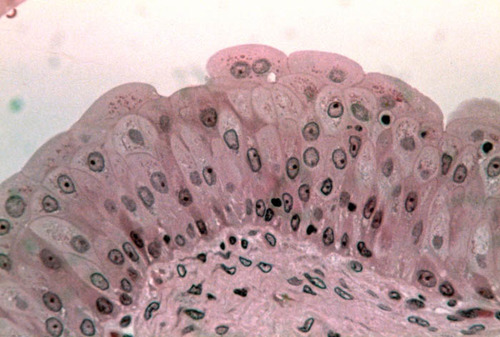

stratified squamous

consist of several layers; functions in protection

keratinization

Process of hardening, dehydration, and keratin accumulation that occurs in epidermal cells as they migrate outward

stratum corneum